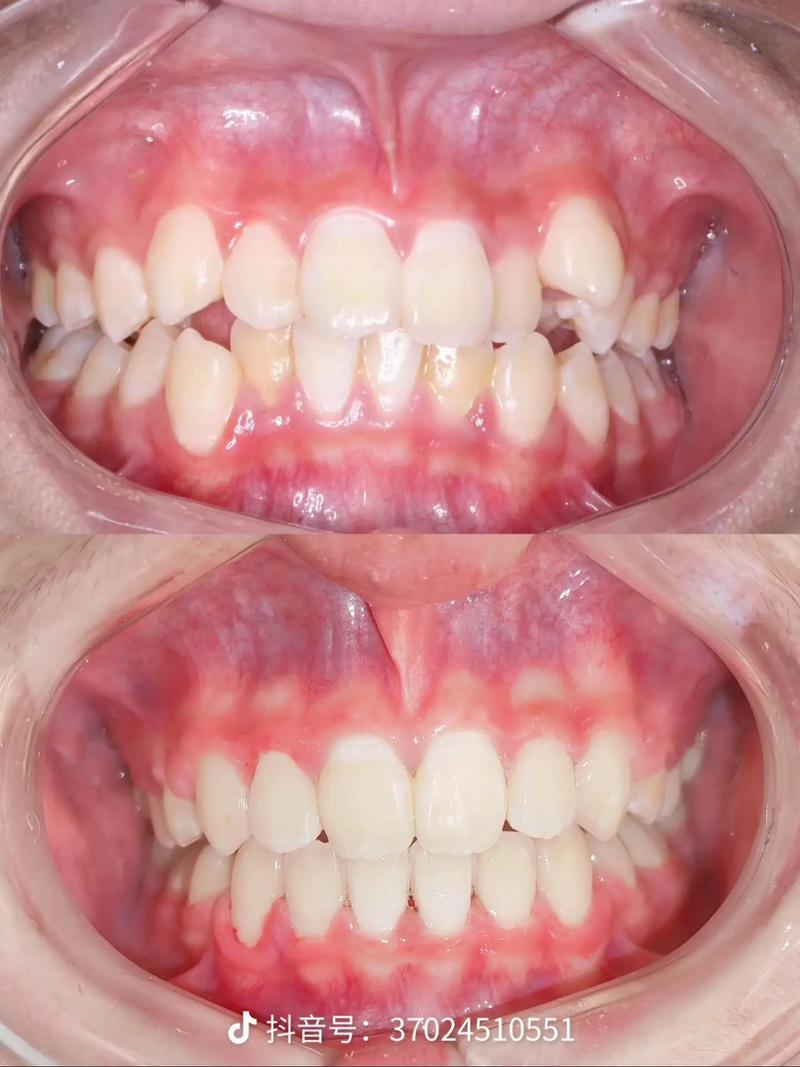

- 拔牙后直接排齐: 在创造的空间内,通过固定矫治器(托槽和弓丝)将重叠的牙齿(通常是尖牙)逐步移动到正确的位置。

- 调整咬合与美观: 在牙齿排齐后,精细调整咬合关系,确保尖牙引导功能正常,前牙美观协调,可能需要配合II类或III类颌间牵引。

保持: 治疗结束后,必须严格佩戴保持器(通常需要长期甚至终身佩戴),因为这类牙齿位置异常复发风险相对较高。